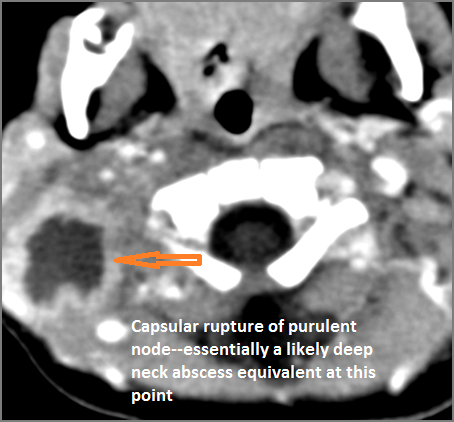

There is reactive cervical lymphadenopathy. |

Yes | NA |

|

If there is suppurative cervical adenopathy the purulent material outside the lymph node(s) capsule(s). |

No | NA |